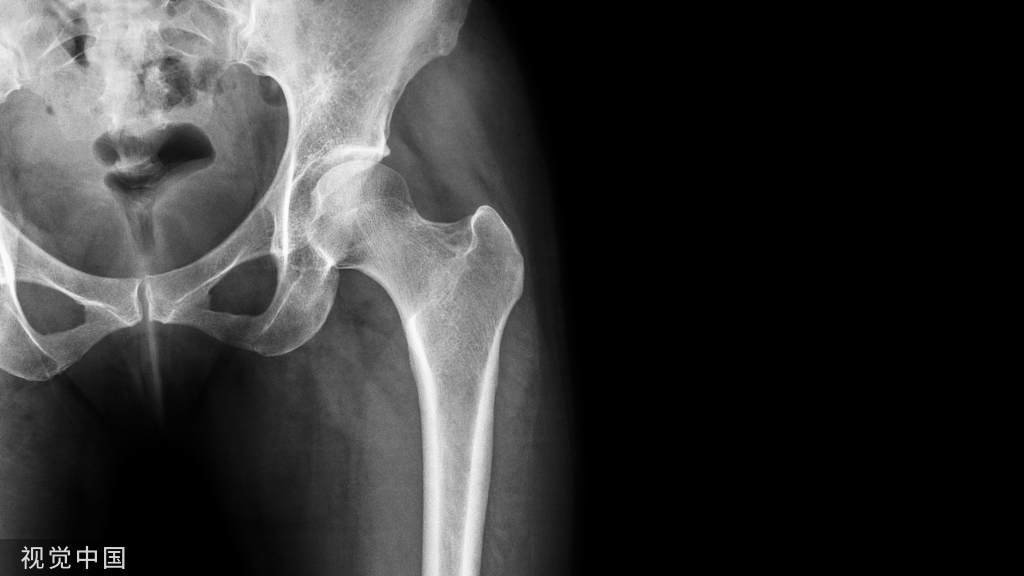

1、自体骨移植取骨部位

2、不同取骨区的特点 皮质骨---较多骨形成蛋白(BMP),细胞成分少,成活较困难,成活后吸收少。

• 松质骨---富含细胞成分,疏松结构有利于新血管生长,较易成活,吸收较多。